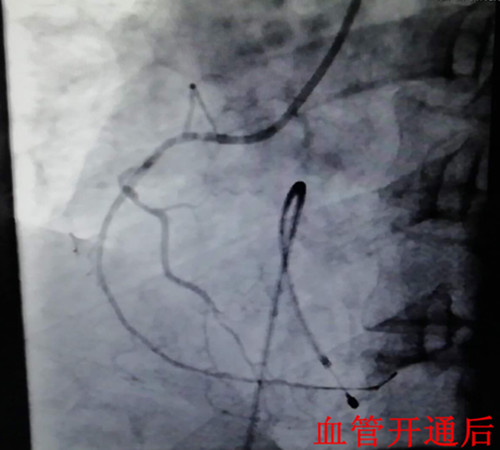

在一阵有效地抢救之后,患者在气管插管、呼吸机辅助呼吸下,先行心脏临时起搏器置入,后行左右冠状动脉造影,造影显示:右冠状动脉呈鼠尾状,开口5mm处100%闭塞,旋支血管中远段60—99%弥漫狭窄病变。手术者立即开通右冠状动脉,尽管患者在手术过程中不断出现室速室颤,血压下降,但随着右冠状动脉远端血流恢复,患者终于生命体征趋于平稳,安全返回监护室继续下一步治疗。